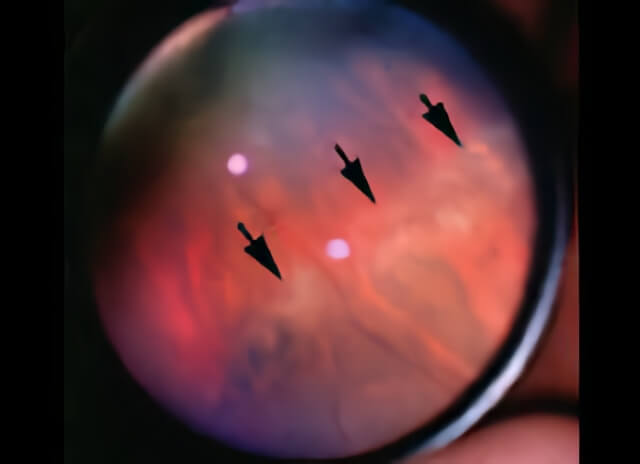

Lattice degeneration appears as areas of peripheral retinal pigmentation and whitening, seen here between the arrows.

The clinical appearance is that of circumferentially oriented cigar-shaped areas of retinal whitening and/or pigmentation seen in the anterior retina. The retina within lattice is exceptionally thin and the vitreous jelly is abnormally adherent to the edges of the lesions. This thinning of the retina and the abnormal vitreous attachment predisposes these areas to tear when the vitreous gel pulls on the retina.

Arrows in this photo indicate the edge of lattice degeneration as viewed by your doctor.